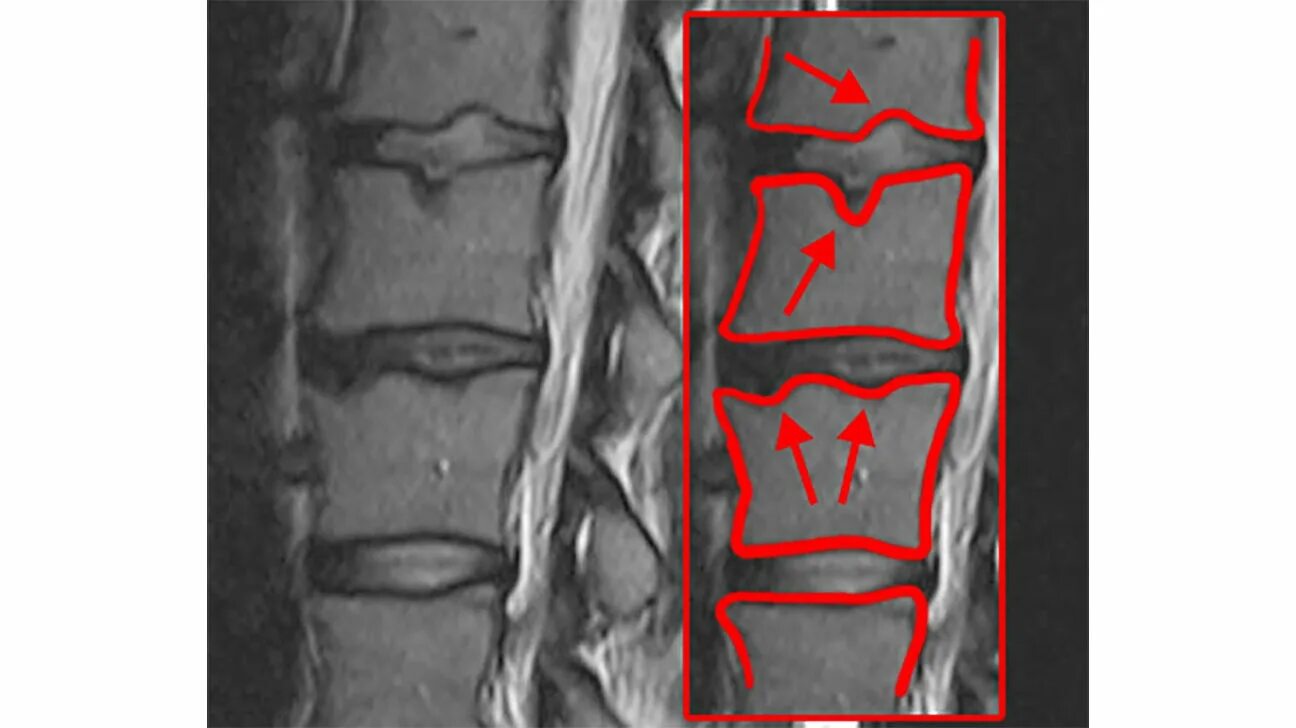

Протрузии шморля